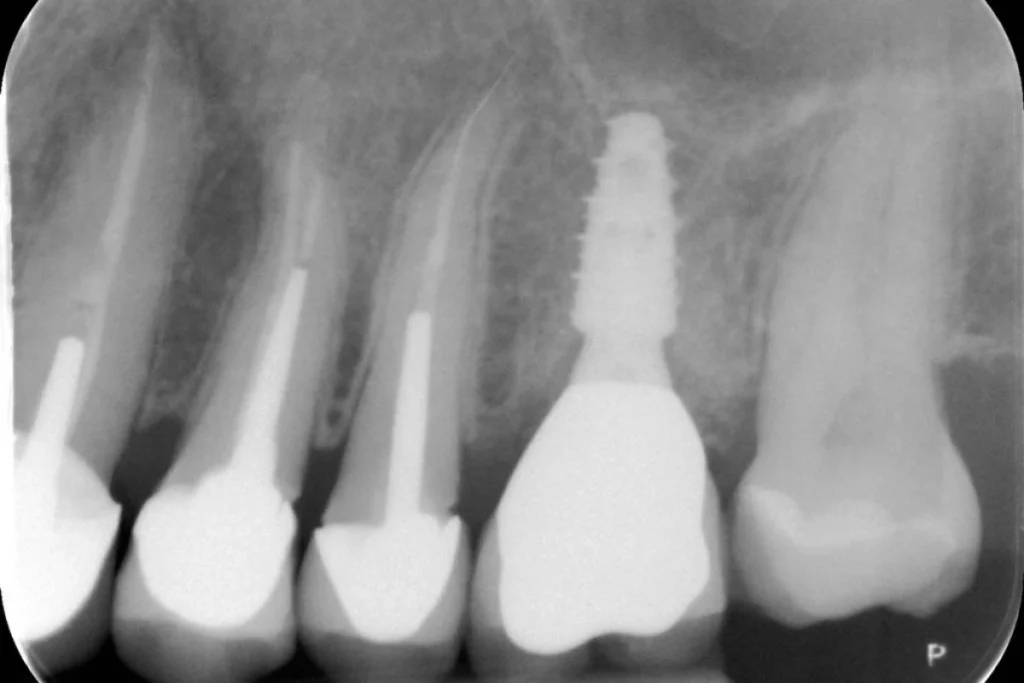

Nous vous présentons le cas de Mme B. 53 ans, qui consulte suite à des douleurs sur sa molaire supérieure gauche.

Après un examen clinique et radiographique, le verdict tombe… la dent n’est malheureusement plus conservable.

Après lui avoir exposé les différentes solutions, Madame B. souhaite remplacer sa dent par un implant. C’est la solution de choix pour retrouver une dent fixe sans avoir à abimer les dents de part et d’autre. L’analyse du scanner nous permet de proposer à Madame B. une extraction implantation immédiate. Il s’agit de réaliser en une seule et même séance l’extraction de la dent condamnée et la mise en place de l’implant dentaire.

Cela permet d’éviter une 2ème chirurgie à notre patiente et de raccourcir la durée du traitement de plusieurs mois. Un comblement osseux est réalisé le jour de l’intervention.

3 mois après la pose de l’implant, la patiente peut retrouver une dent fonctionnelle et esthétique.